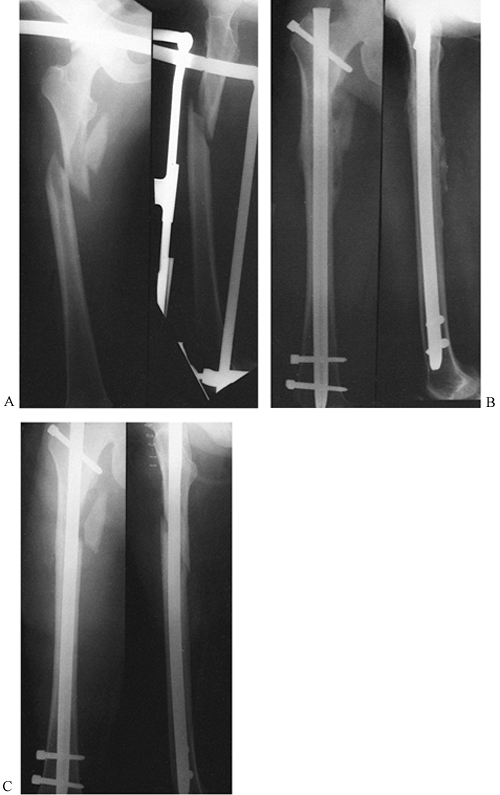

stabilization far outweigh the risks (Fig. 19.5).

![]() |

|

Figure 19.5. Percutaneous cannulated screw fixation of an impacted, Garden stage I, subcapital hip fracture. A: AP radiograph of the hip fracture prior to fixation. B: Lateral radiograph. C: AP radiograph after cannulated screw fixation. D: Lateral radiograph; ideally, the screws could be spread out somewhat more and be more parallel.

fractures, whether displaced or undisplaced, with internal fixation

rather than prosthetic replacement (Fig. 19.5, Fig. 19.6). Even in displaced fractures such as a Garden stage IV where treatment is delayed, good internal fixation in anatomic

Figure 19.6. Cannulated screw fixation of a displaced subcapital hip fracture: A: AP radiograph showing a fully displaced Garden stage IV subcapital fracture. B: Lateral radiograph of the displaced fracture. C: AP radiograph after closed reduction and cannulated screw fixation. D: Lateral radiograph after fixation.